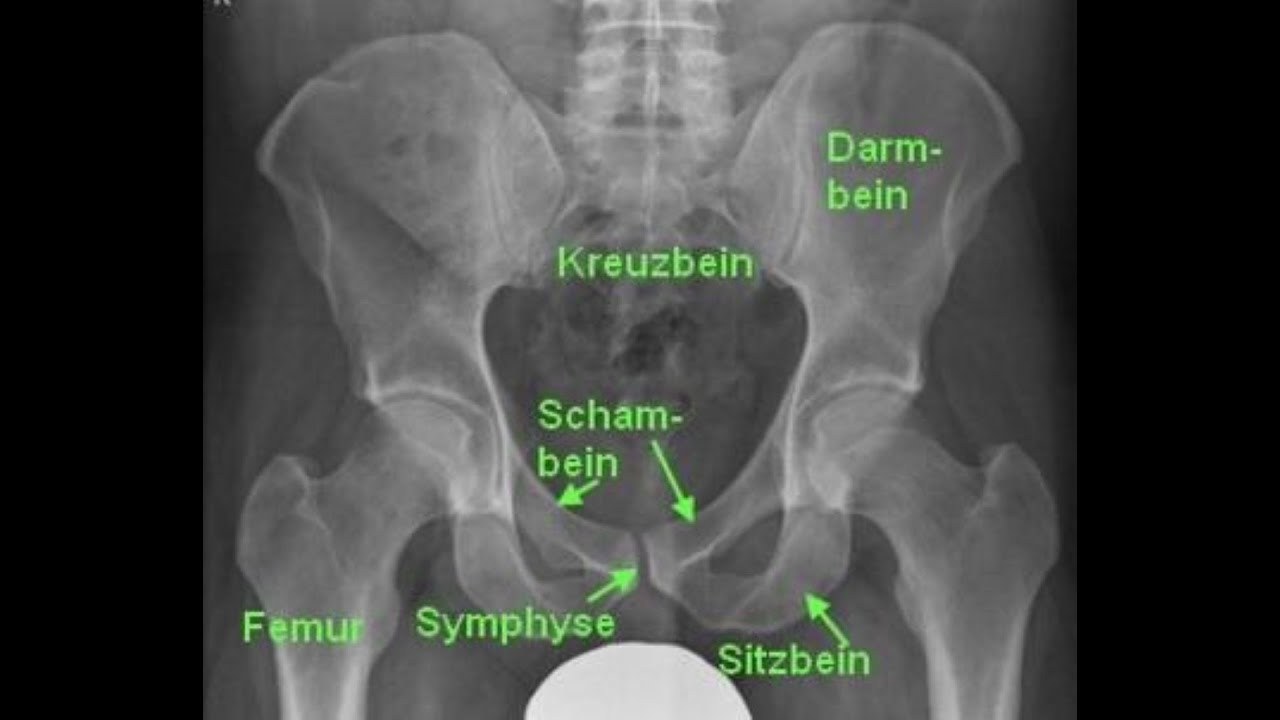

Die Organe im kleinen Becken der Frau - osteopathisch erklärt

Описание: In diesem Video erkläre ich kurz und verständlich das kleine Becken bei der Frau.

Neben den knöchernen Strukturen und erläutere ich leicht und verständlich die Zusammenhänge zwischen Enddarm, Gebärmutter und Blase.